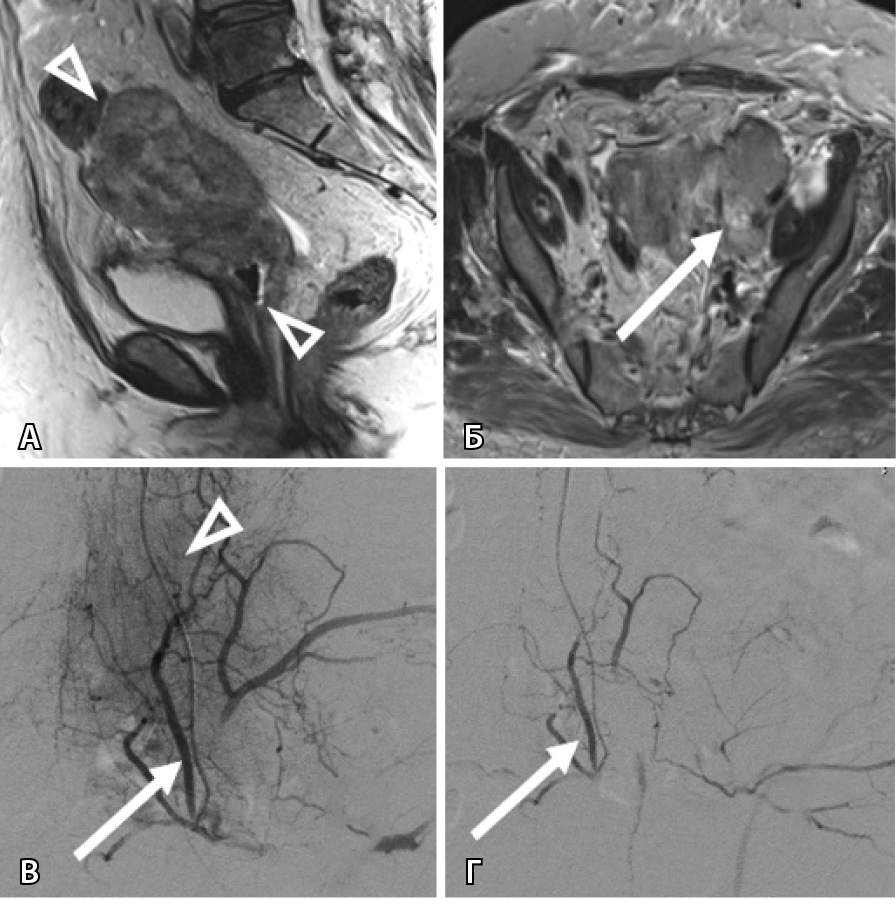

При достижении опухолью боковой стенки малого таза (7 наблюдений) отмечалась дополнительная сеть афферентов от подвздошно-поясничной артерии, которая в норме не участвует в кровоснабжении тазовых органов (рис. 3).

Рис. 3. Женщина 64 лет, рак шейки матки, рецидив через 8 месяцев после системной химиотерапии, профузное маточное кровотечение: А – магнитно-резонансная томография в сагиттальной проекции: опухоль распространяется от дна тела матки до средней трети влагалища (треугольные стрелки); Б – магнитно-резонансная томография в аксиальной проекции демонстрирует опухолевый фрагмент, достигающий боковой стенки малого таза (стрелка); В – этап трансартериальной химиоэмболизации: на ангиограмме определяется сеть опухолевых афферентов (треугольная стрелка), отходящих от подвздошно-поясничной артерии (стрелка); Г – результат эмболизации: опухолевые афференты не контрастируются, проходимость подвздошно-поясничной артерии сохранена (стрелка)